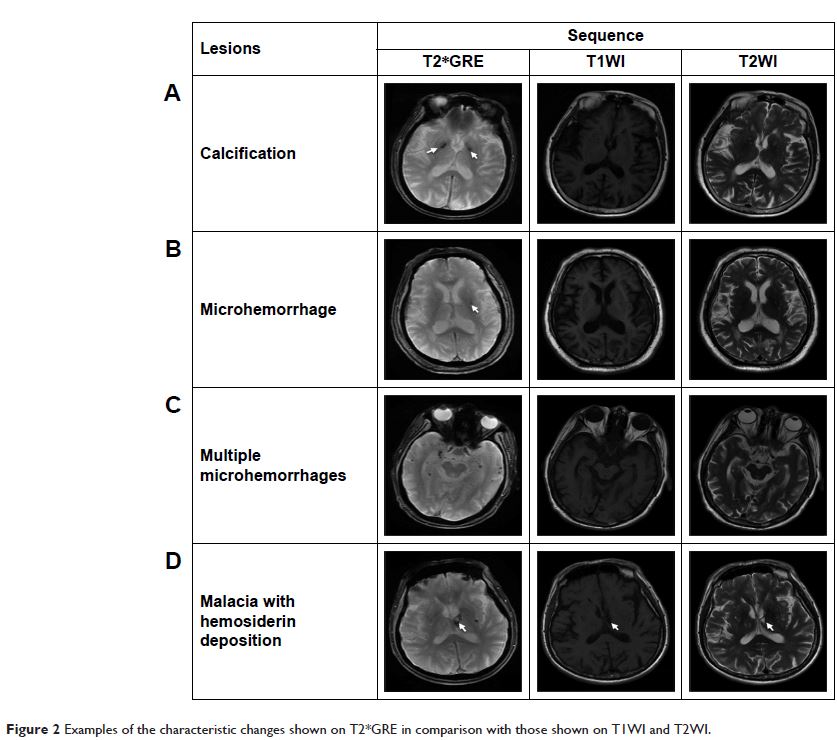

- 作者:Hui Guo, William Siu, Ryan CN D’Arcy, Sandra E Black, Lukas A Grajauskas, Sonia Singh, Yunting Zhang, Kenneth Rockwood, Xiaowei Song

- 期刊:Clinical Interventions in Aging